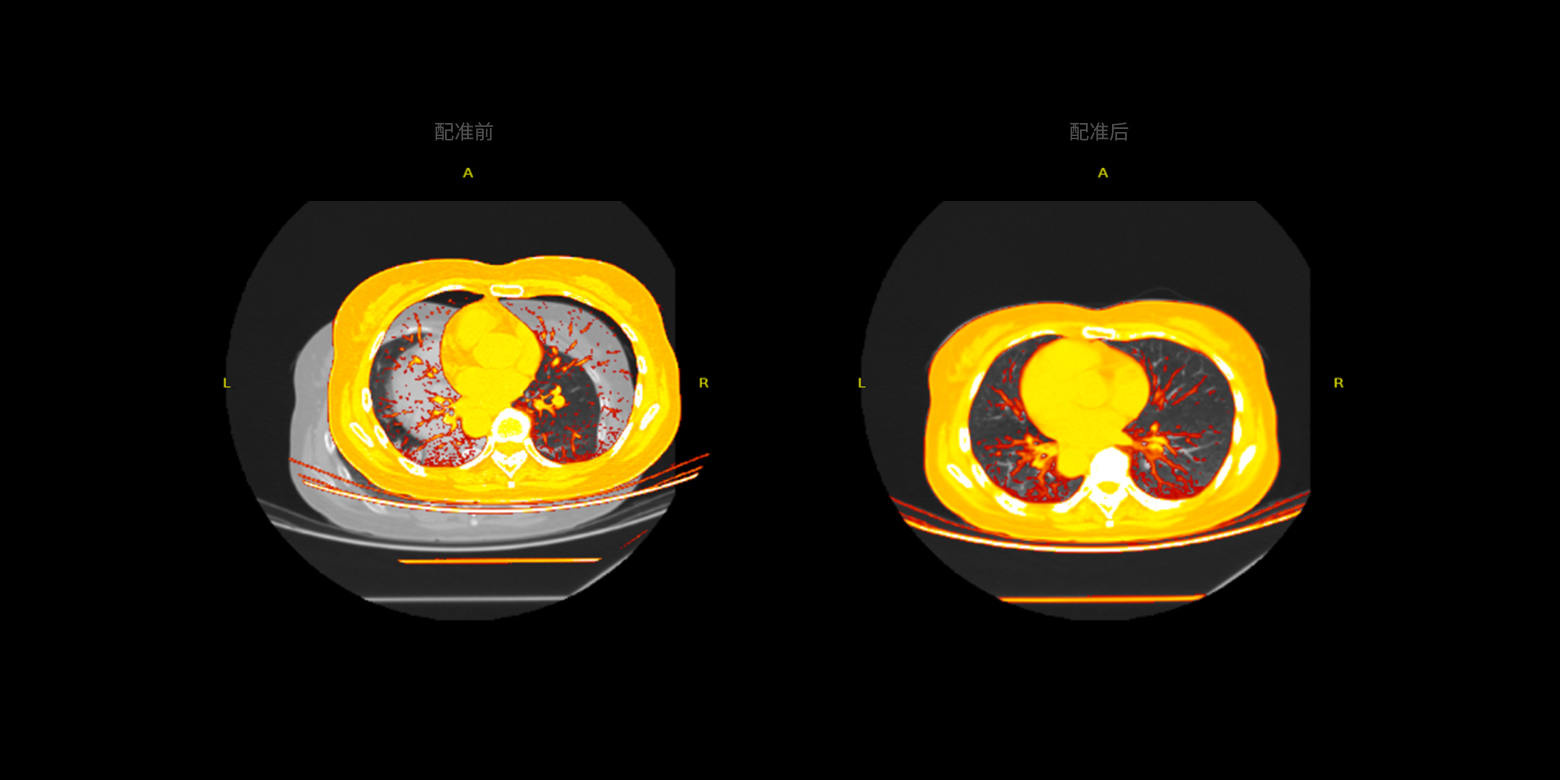

- 01多模式的數據配準

01 / 05

多模式的數據配準

提供多模式的數據配準,可融合不同模式或不同序列的圖像數據,例如同一(器官)部位的CT、MRI、PET數據配準,進而精準地對病灶作定性或定量的風險分析。

01 / 05

多模式的數據配準

提供多模式的數據配準,可融合不同模式或不同序列的圖像數據,例如同一(器官)部位的CT、MRI、PET數據配準,進而精準地對病灶作定性或定量的風險分析。